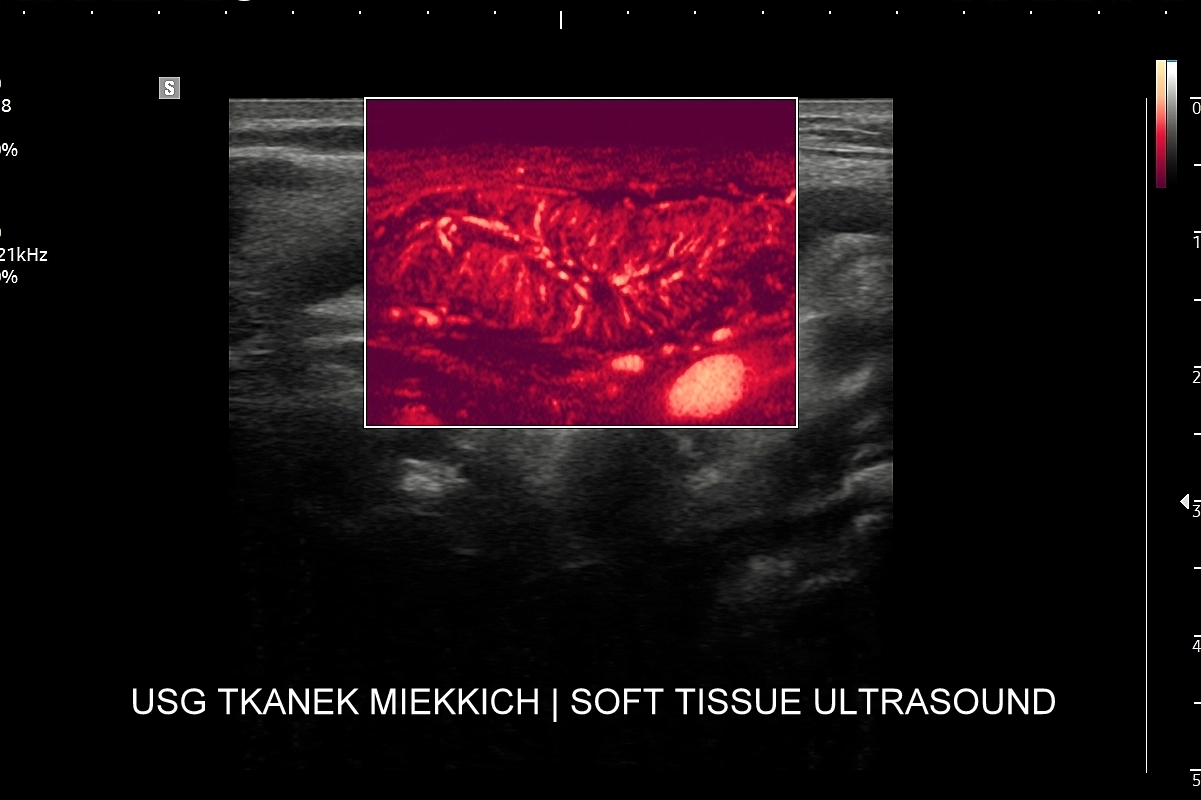

Badanie USG skóry i powłok jest metodą diagnostyczną, która swoją czułością oraz dokładnością przewyższa w ocenie patologii powłok badanie rezonansem magnetycznym. W obrębie powłok ciała w badaniu USG najczęściej rozpoznaje się różnorodne guzy oraz stany zapalne. Wśród guzów dominują łagodne tłuszczaki, kaszaki i torbiele inkluzyjne, a także przepukliny. U młodszych pacjentów często wykrywa się naczyniaki. Rzadziej spotkane są guzy złośliwe jak mięsaki, czy przerzuty nowotworowe. W pracowni USG dr Szczepańskiego poza wizualną oceną guzów powłok przeprowadzana jest ich ocena biologii w kontekście cech złośliwości i oceny przewidywalnego tempa wzrostu.

USG tkanek miękkich obejmuje ocenę diagnostyczną opisanych już wcześniej patologii, ale także zmian miękkotkankowych położonych w głębszych warstwach powłok oraz obszarach podpowięziowych takich jak chrząstki, ciała tłuszczowe, mięśnie, ścięgna, troczki, pochewki ścięgniste, stawy i gangliony, torbiele wrodzone, czy aparat paznokciowy.

Aparatura do USG skóry

Pracownia dr Tomasza Szczepańskiego świadcząca usługę USG skóry we Wrocławiu, jako jedna z kilku w Polsce, wyposażona jest w aparaturę dysponującą zaawansowaną technologią, oprogramowaniem oraz specjalistycznymi sondami umożliwiającymi obrazowanie skóry o niestandardowo wysokiej rozdzielczości, a także diagnostykę funkcjonalną i biologiczną zmian chorobowych w skórze oraz w powłokach ciała.